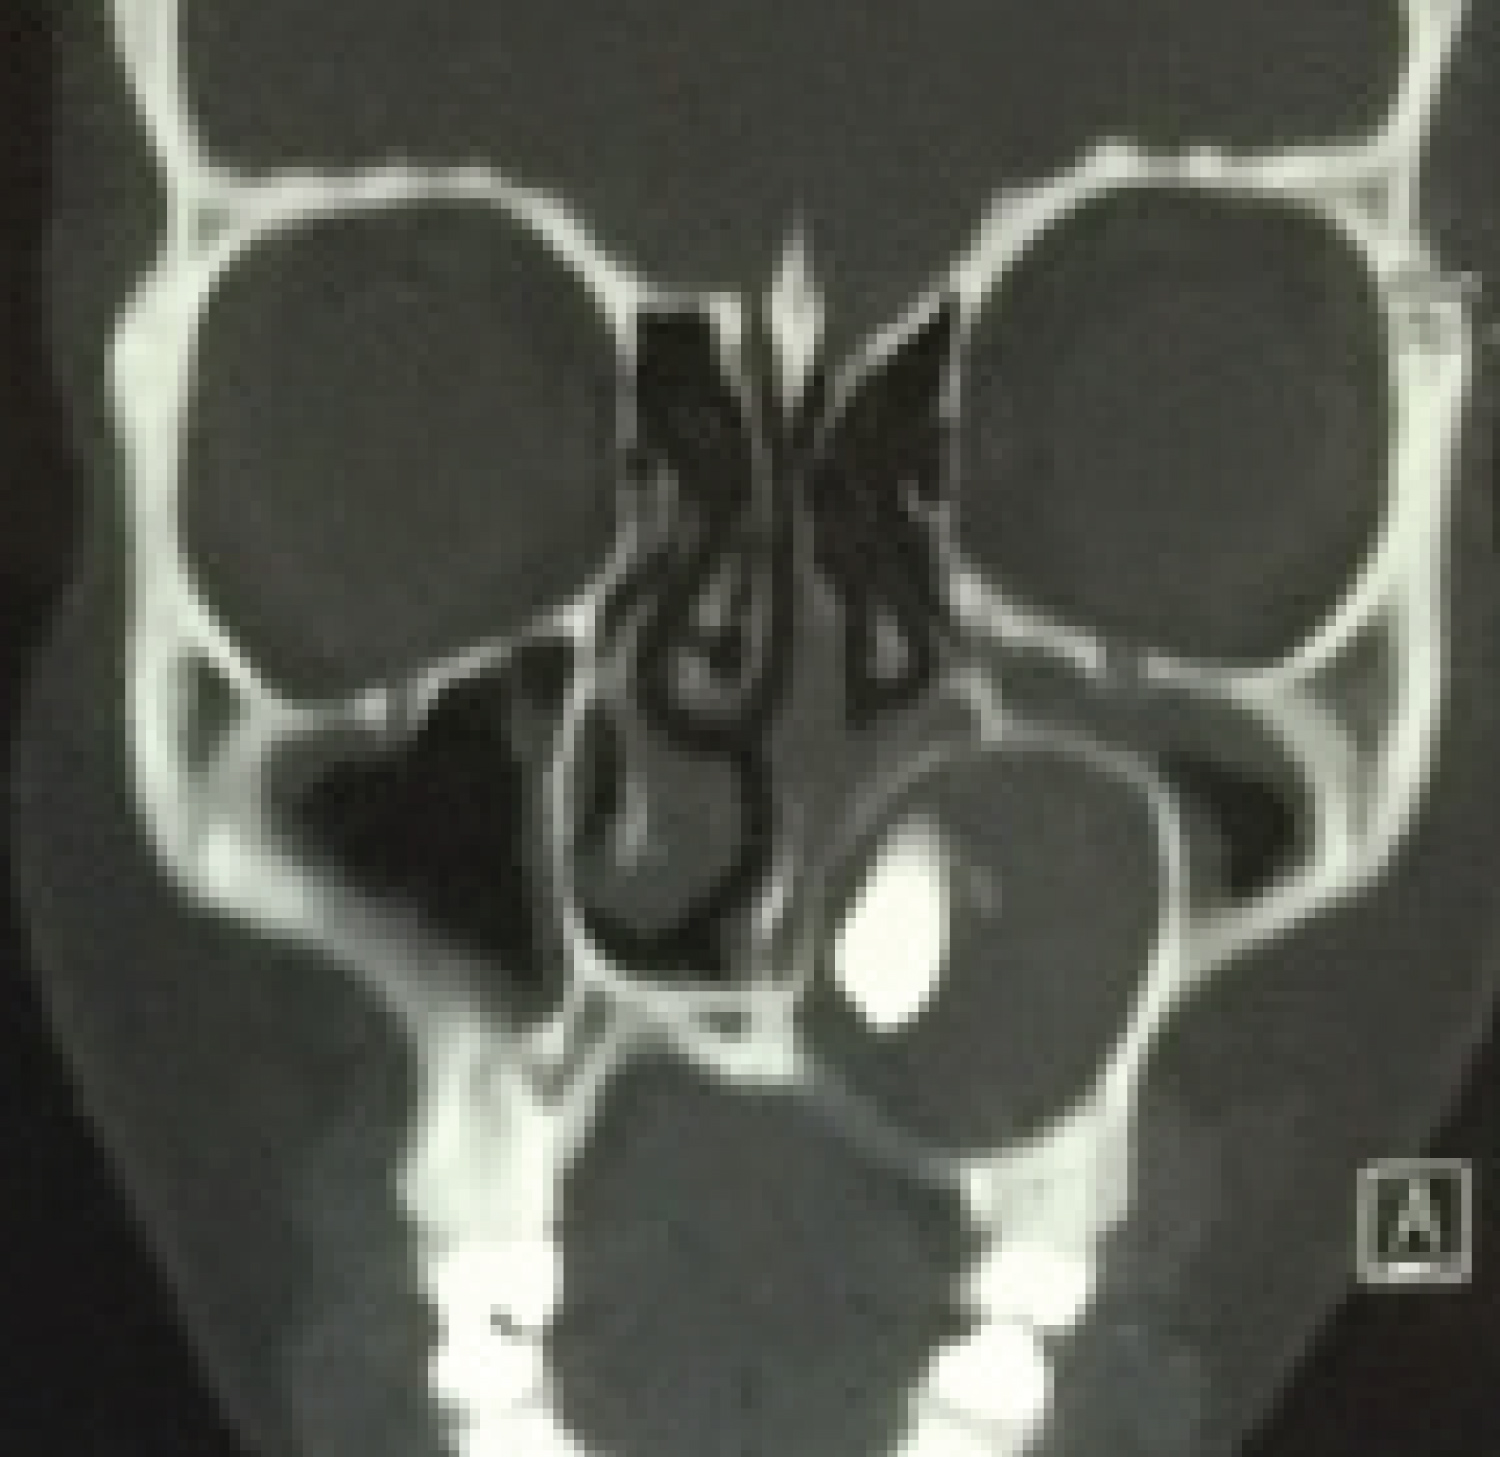

At 4-year follow-up, the patient showed no signs of clinical or imaging recurrence (Figure 4).

Figure 4: Image in a coronal section shows no sign of recurrence. View Figure 4